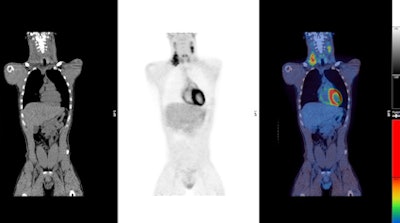

PET imaging was performed on full-ring PET or PET/CT scanners at centers within the U.K. National Cancer Research Institute (NCRI) PET Research Network. PET images were negative among 426 patients (75%). Individuals who had positive PET results continued on to receive additional radiotherapy.